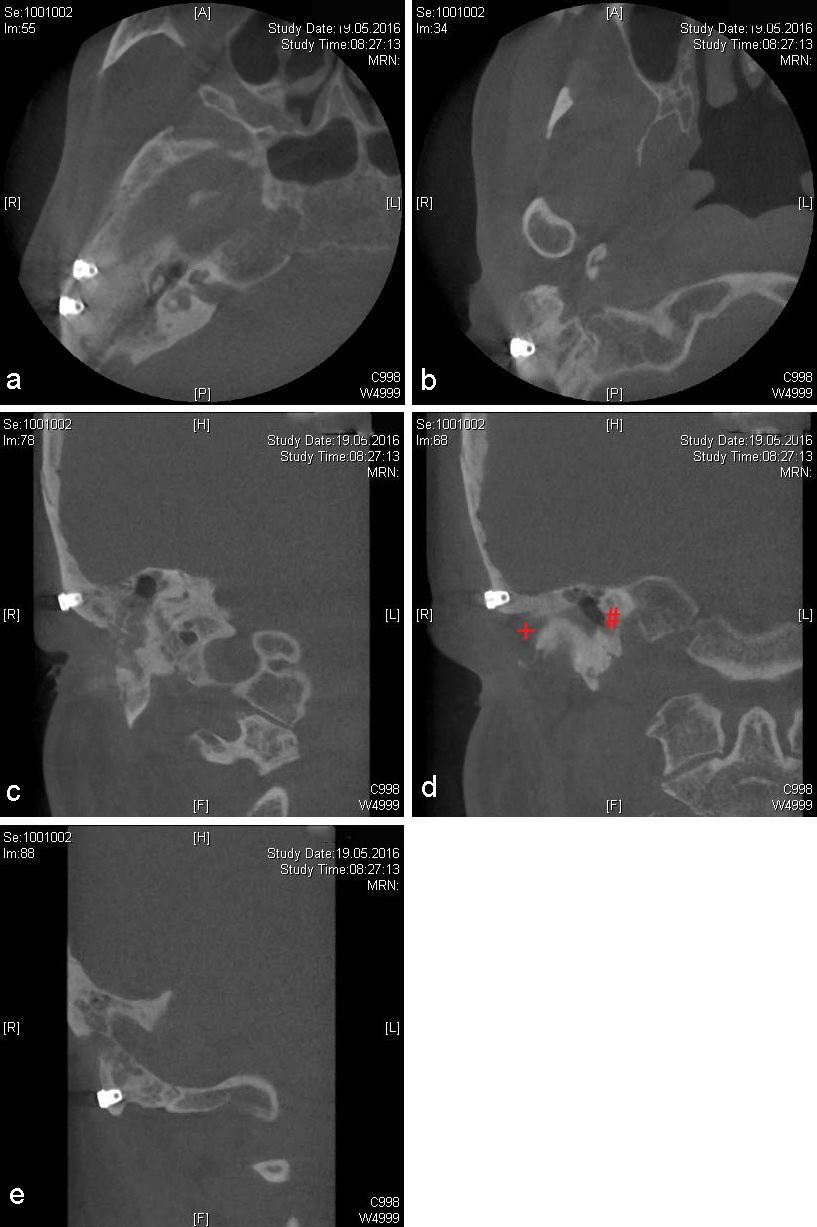

Under general anesthesia and including perioperative systemic antibiotic treatment (Cefuroxim 2x 500 mg daily per os), three endosseous screw implants [11] were inserted (Southern implants, 4x3.75 mm, Gauteng, South Africa). A duplicate of the interim epithesis was used as a drilling splint, based on the preoperative planing (Figure 5 [Fig. 5]). Two implants were inserted cranialy to the external meatus acusticus, and the remaining one in the residual mastoid process, thus avoiding pneumatized areas (Figure 6 [Fig. 6]). The healing period proved uneventful.

Figure 6: Postoperative CBCT-imaging. a: Axial section. Both cranial implant positions. b: Axial section. Caudal implant position. c: Coronal section. First cranial implant position. d: Coronal section. Second cranial implant position, red plus marking the external meatus acusticus, and red diamond indicating the cochlea. e: Coronal section. Caudal implant position.